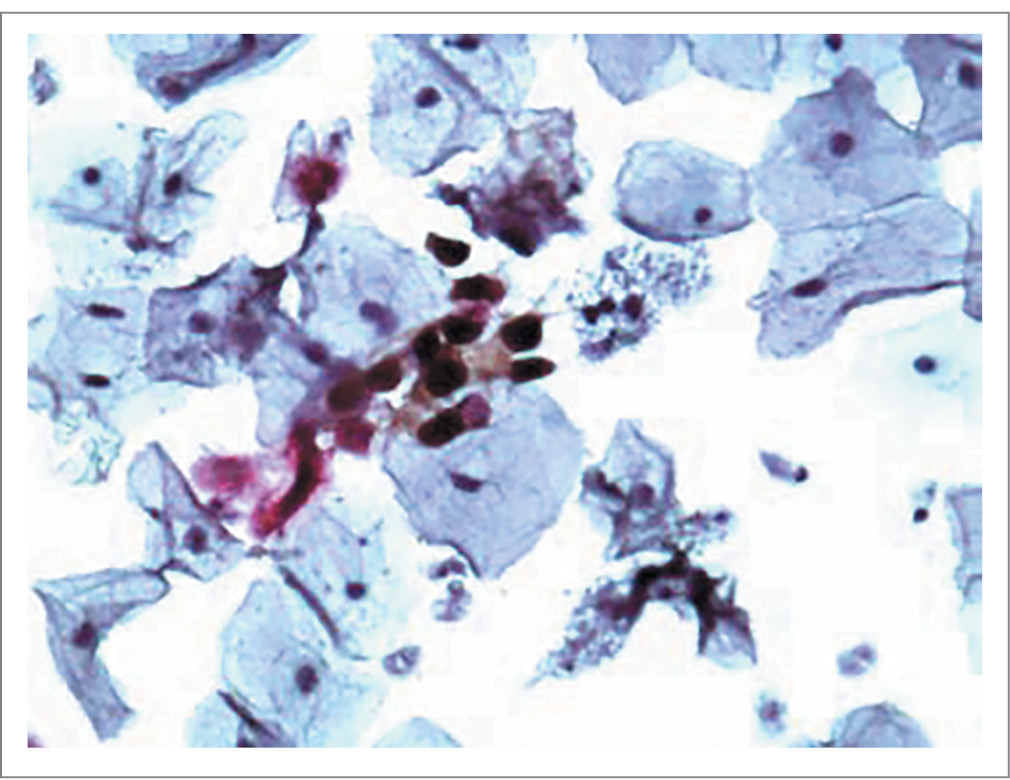

Дана оценка частоте позитивного результата двойного окрашивания p16/Ki-67 в эпителии образцов от 75 пациенток: с CIN1, CIN2,3, с латентной формой ВПЧ-инфекции и группы контроля. Позитивный тест двойного окрашивания с помощью ИЦХ-исследования эпителия отражал наличие коэкспрессии p16/Ki-67 (рис. 1). На примере позитивного теста показано двойное окрашивание маркеров в цервикальном эпителии пациентки 2-й основной группы с HSIL (High-grade Squamous Intraepithelial Lesion) на фоне ВПЧ-16.

Рис. 1. Коэкспрессия p16/Ki-67. CINtec PLUS positive. Sure Path, HSIL, ×200. ВПЧ-16.

Fig. 1. Co-expression of p16 / Ki-67. CINtec PLUS positive. Sure Path, HSIL, × 200. HPV-16.

Уровень биомаркеров можно оценивать не только в эпителиальных клетках при проведении иммуноцитохимии (коричневое цитоплазматическое и/или ядерное окрашивание указывает на наличие р16, красное окрашивание ядра – на присутствие Ki-67), но и посредством иммуногистохимии. Если ИЦХ-исследование позволяет установить факт экспрессии изучаемого маркера, то по данным иммуногистохимии можно детализировать выраженность признаков окрашивания. По данным иммуногистохимического исследования экспрессии p16 в биоптатах пациенток с ВПЧ-ассоциированными CIN2–CIN3 были выявлены более выраженная интенсивность реакции, протяженность окраски, более высокая частота обнаружения ядерной метки, 3-кратное повышение величины иммуногистохимического индекса в сравнении с CIN1 [5]. Одновременное определение р16 и Ki-67 имеет очевидные преимущества как с позиции более высокой информативности двух маркеров, так и неинвазивности забора материала, меньшей трудоемкости при выполнении ИЦХ-исследования, более быстрого получения результата.